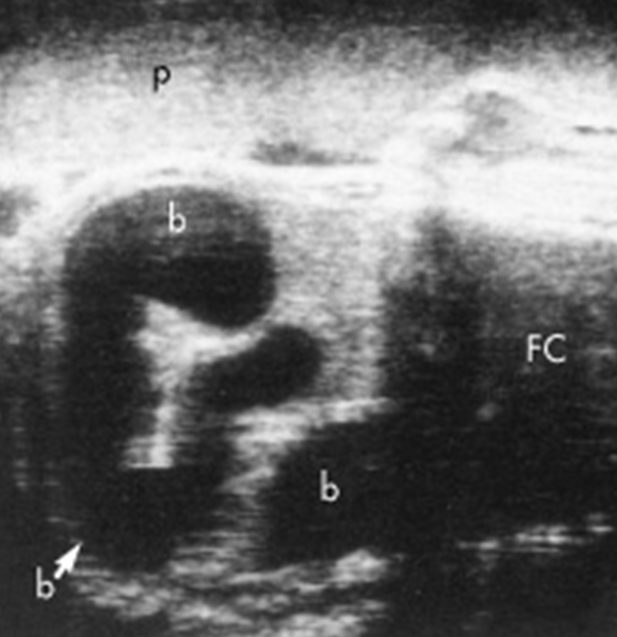

Fetal ascites